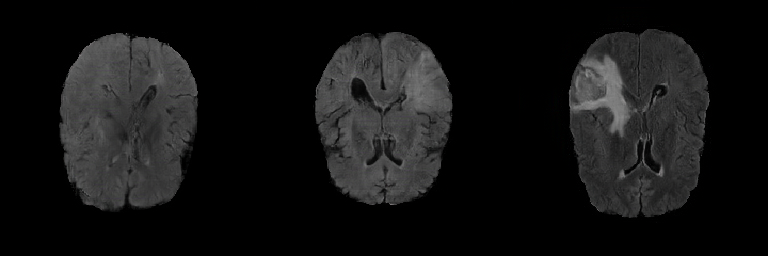

Generated Images Figure 5 shows the generated brain tumor FLAIR samples from -GAN-GP, PGGAN, and PGGAN-SSIM in AXI. The generated samples from all models look realistic and are close to the real images, where the white areas (Gliomas area) are concentrated and unified, indicating the training stability with gradient penalty. However, the samples from -GAN-GP are blurry, and the detailed brain features disappear since the loss of image information becomes serious when the image resolution increases in -GAN-GP. The generated samples from PGGAN and PGGAN-SSIM have clear and realistic brain features (FLAIR texture and tumor appearance) with diversity, which illustrates that PGGAN architecture is a well-suited model to generate brain MR images.